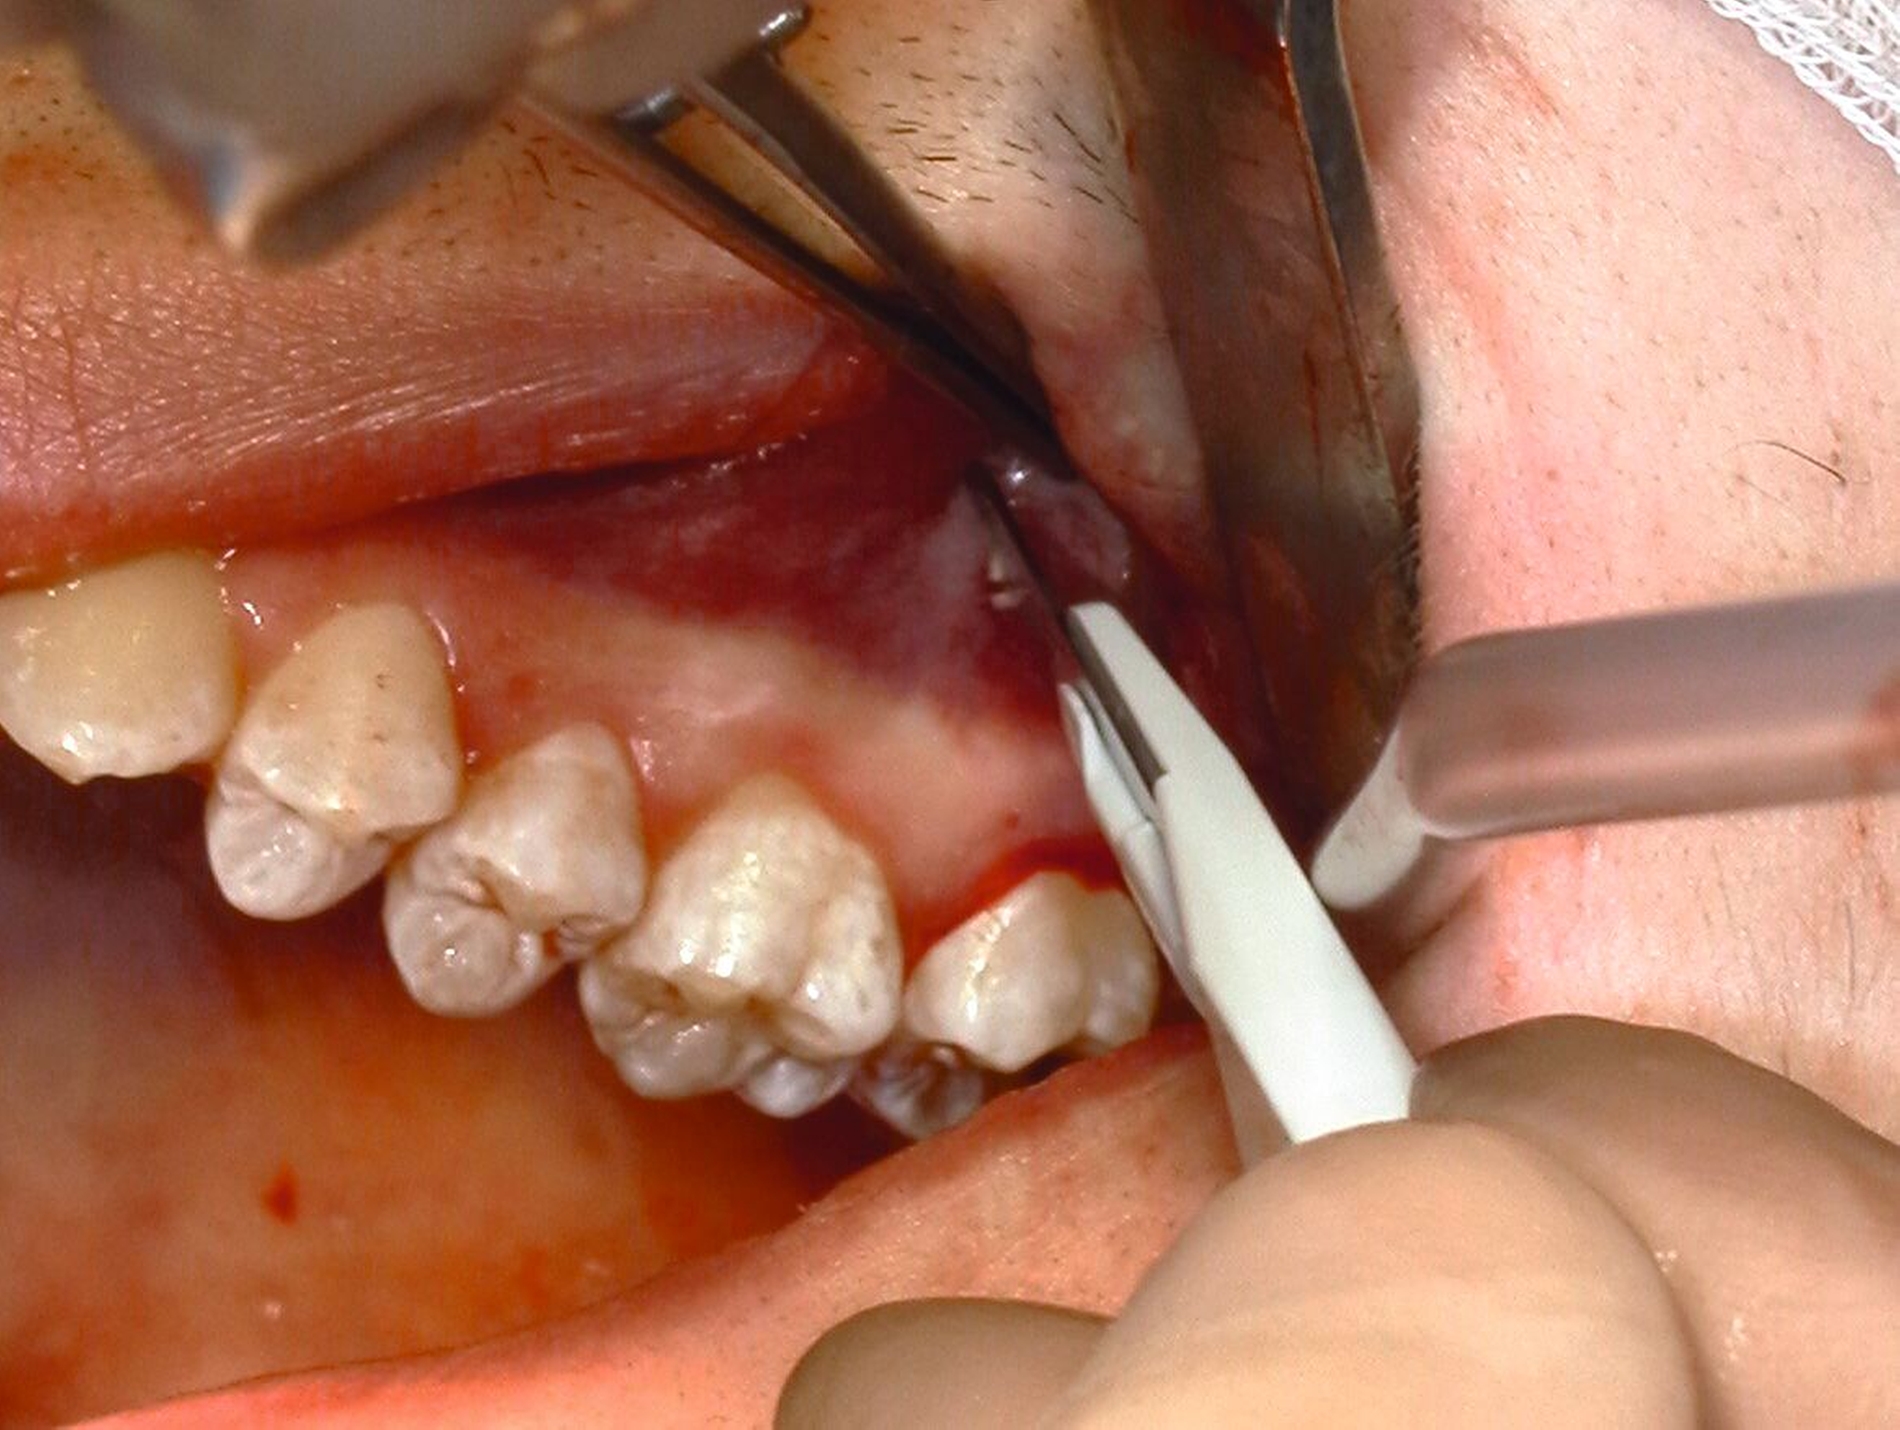

Allgemein kann eine präemptive Analgesie in Form einer präoperativen Gabe von 400-600 mg Ibuprofen eine Stunde vor dem Eingriff verabreicht werden, was sich positiv auf das Schmerzempfinden und den Bedarf postoperativ auswirken kann [Gutwald et al., 2019]. Zu Beginn des Eingriffs kann eine Lokalanästhesie durchgeführt werden. Bei dieser kommen entweder eine Oberflächenanästhesie, eine Infiltrationsanästhesie, eine Leitungsanästhesie (N. alveolaris inferior im Unterkiefer, N. palatinus major im Oberkiefer) oder eine intraligamentäre Anästhesie zum Einsatz (Abbildung 6) [Daubländer et al., 2016].

Zur Entfernung der unteren Weisheitszähne wird im Unterkiefer zunächst der aufsteigende Ast im Bereich der Linea obliqua palpiert. Verwendet man eine Pinzette zur Markierung (Abbildung 7), erfolgt die Schnittführung von dieser im senkrechten Winkel zum Knochen distal auf den zweiten Molaren zu, weiter im PA-Spalt bis mesial des zweiten Molaren. Liegt der Zahn tief verlagert oder anguliert, sollte man zur besseren Übersicht einen größeren Entlastungsschnitt unter Schutz des N. mentalis wählen.